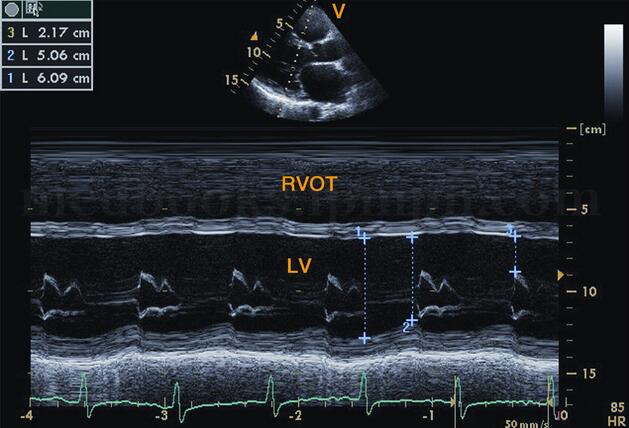

图2‐1‐183 二尖瓣口水平M型超声左室呈“大心腔,小瓣口”改变,E峰至室间隔距离明显增大

超声描述 全心扩大,以左心为主,左室舒张末期内径78.5mm;主动脉振幅减低,呈充盈不足表现;二尖瓣开放相对小,左室呈“大心腔,小瓣口”,E峰至室间隔距离(EPSS)增大为25﹒6cm;室壁运动弥漫性减弱,左室射血分数34.5%;二尖瓣口E峰明显大于A,呈限制性充盈,二、三尖瓣中度反流;少量心包积液。

(1)二尖瓣波群见左室明显增大,右室扩大,二尖瓣前后叶开放幅度变小,呈“钻石样”改变,形成“大心腔,小开口”,但前后叶仍呈镜像运动。E峰至室间隔距离(EPSS)明显增大,一般>10mm。

(2)室间隔及左室壁振幅弥漫性减低,以左室后壁为著。后壁振幅≤7mm,室间隔振幅≤3mm(图2‐1‐186)。